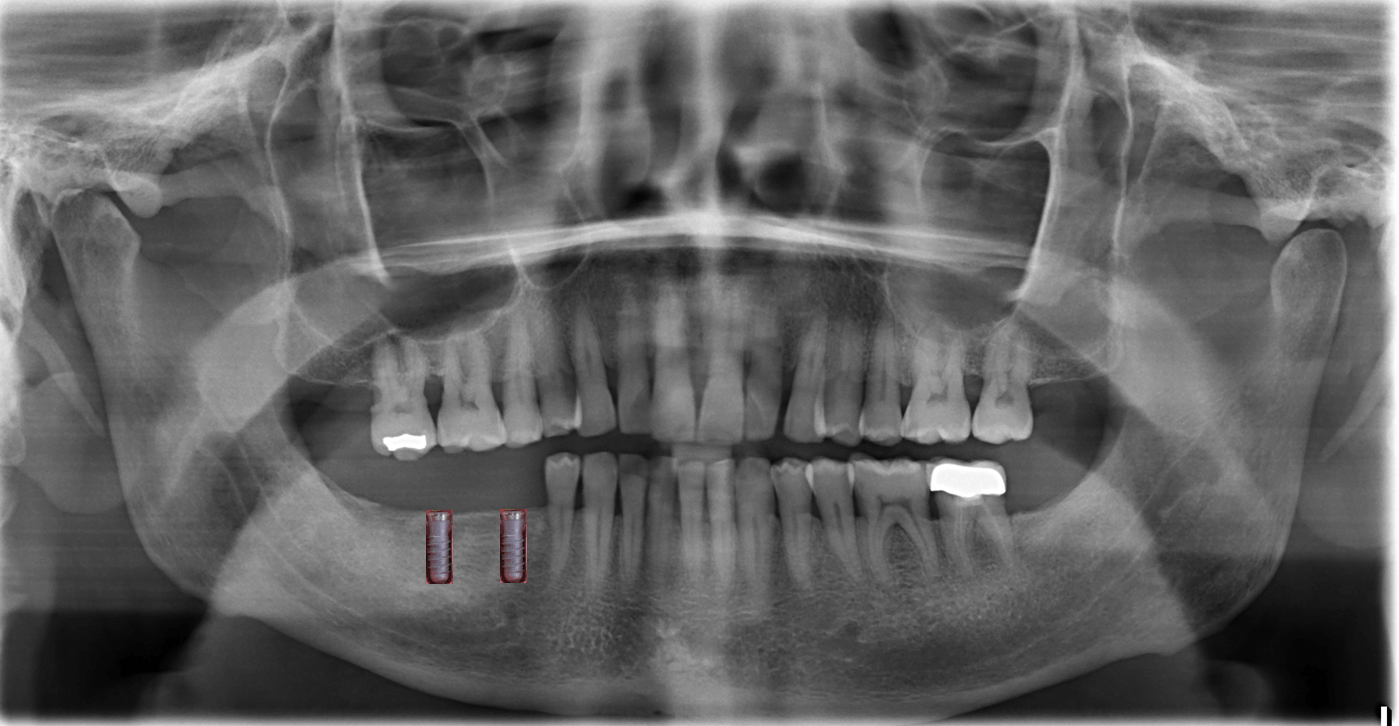

اشعة X و 3D والفحص

أساس الخطة النهائية

يتم إجراء فحص ثلاثي الأبعاد "التصوير المقطعي بالحجم الرقمي" في مركز DVT هامبورغ ، Lerchenfeld 14 ، 22081 هامبورغ ، هاتف 040-2269-4990. سوف يعطونك القرص المضغوط ، الذي سنقرأه هنا.